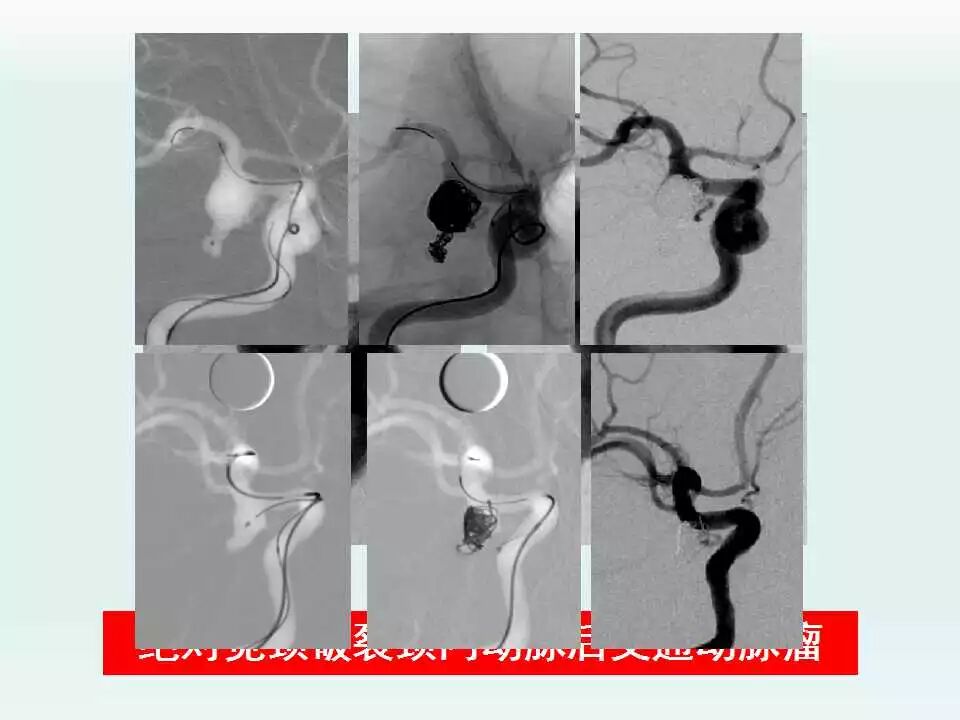

2003年开始神经介入工作,5年前在安徽省率先成立脑血管亚专业病区,每年的脑血管造影和血管内治疗颅内动脉瘤、脑动静脉畸形、颈内动脉海绵窦瘘及硬脑膜动静脉瘘等出血性疾病达1000台,并形成了急性期支架辅助弹簧圈治疗破裂宽颈动脉瘤、微小动脉瘤的血管内治疗和复杂动脉瘤的血管内治疗的特色,目前年血管内治疗颅内动脉瘤300例以上。